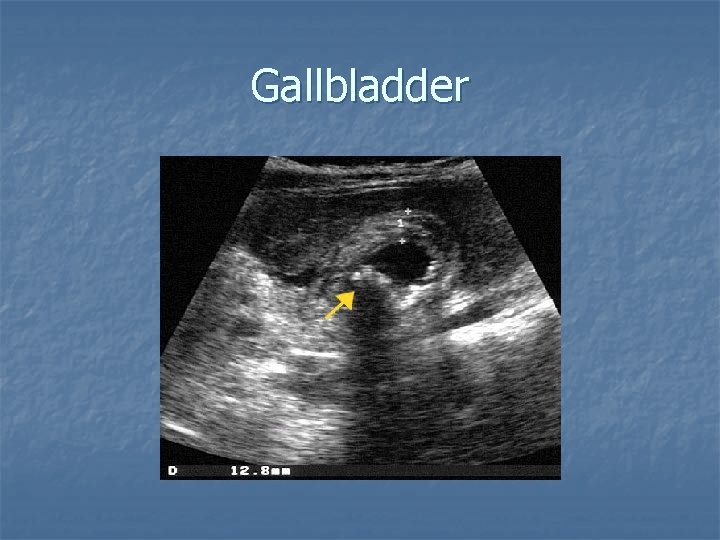

Gallbladder